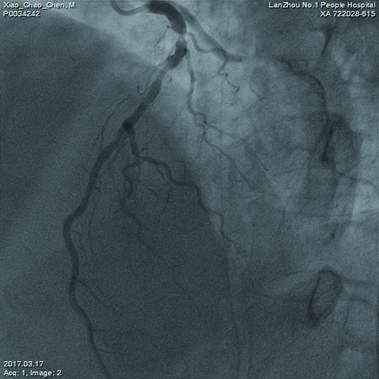

转入重症医学科后18:30行主动脉内球囊反搏,1:1反搏启动,正肾、副肾、多巴安及硝酸甘油微量泵辅助,因呼吸急促(35次/min),氧饱和度下降(80%),19:40呼吸机辅助呼吸。3月15日撤呼吸机,3月17日撤主动脉内囊反搏(IABP)。脱机后冠脉造影示:左前降支及左回旋支远端血流明显好转(图 3)。于3月24日行心脏不停跳冠状动脉搭桥术(OPCAB),左侧乳内动脉→左前降支(LIMA→LAD),升主动脉→大隐静脉→回旋支(AAO→SVG→CX)。术后11 d康复出院。

| 图 3 主动脉内球囊反搏11 d后左前降支血流明显好转 |